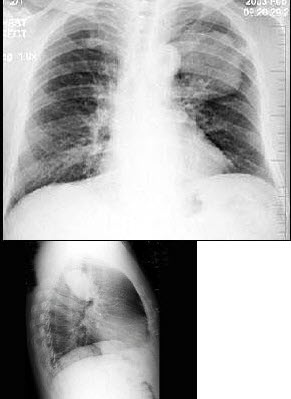

118、单项选择题

男,70岁,胸痛,不咳嗽、发热,X线检查如图,最可能的诊断是()

A.左肺结核瘤

B.左侧叶间积液

C.左肺癌

D.左肺炎性假瘤

E.左肺错构瘤

265、单项选择题

早产儿,男,生后6小时,于生后2小时出现呼吸困难,如图,最可能的诊断为()

A.新生儿肺炎

B.新生儿湿肺

C.新生儿肺出血

D.新生儿呼吸窘迫综合症

E.胎粪吸入综合征

266、单项选择题

男,40岁,胸痛胸闷2月余,胸片如图,最可能的诊断为()

A.右侧恶性胸膜间皮瘤

B.右侧胸腔积液

C.右侧包裹性积液

D.右侧良性胸膜间皮瘤

E.右侧胸膜增厚